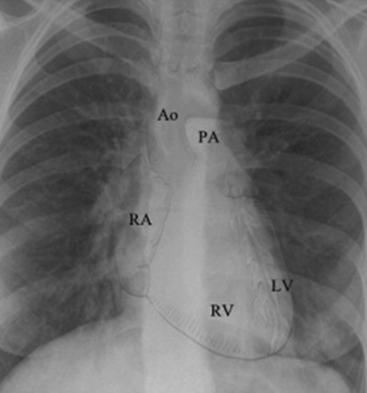

The mediastinum contains the trachea, the two main bronchi, the esophagus, the ascending aorta, the aortic arch (and major branches), the main pulmonary artery (and the proximal right and left pulmonary arteries), the major veins of the heart, the heart, and the thymus (Fig. 10-8). Because most of these structures contain fluid, the radiographic appearance of the mediastinum is that of a single fluid density between the lungs.

image

Fig. 10-8 Cardiac anatomy. This chest radiograph has a graphic overlay of the normal location and identification of the pulmonary artery, aorta, aortic knob, right atrium, right ventricle, and left ventricle as they are positioned in the mediastinum.